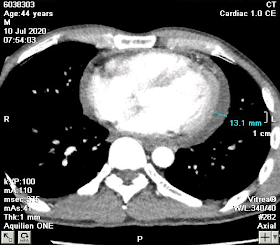

Chest CT-scan on July 10th, 2020 showed suspected mediastinum abscess surrounding the ascending aorta, with saccular aneurysm at the beginning of the aortic arch, and mild pericardial effusion. The differential diagnosis was thoracic aortic aneurysm with surrounding hematoma.